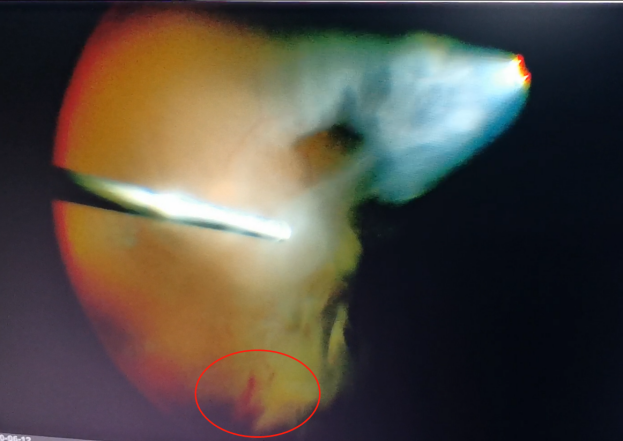

(左為玻璃體切割術(shù)中,明顯可見(jiàn)有積血;右為激光治療后的眼底)

手術(shù)中,醫生們先后為程先生行白內障超聲乳化術(shù)及后入路玻璃體切割術(shù),并置入人工晶體。手術(shù)僅用半個(gè)小時(shí)便順利完成。